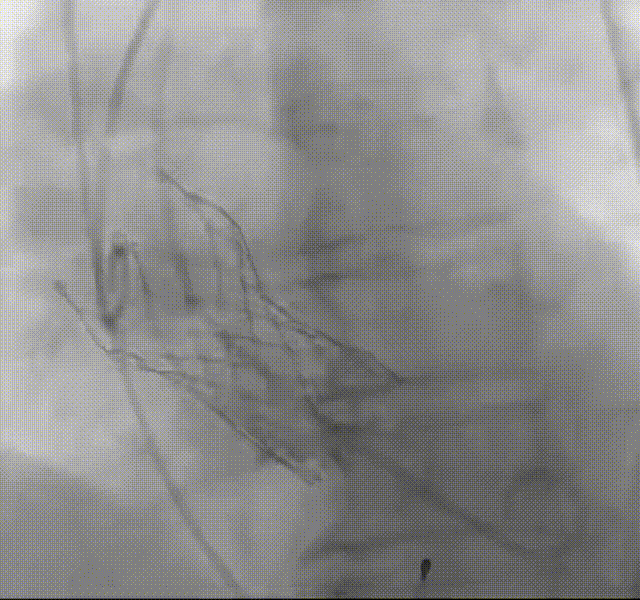

罗建方教授 广东省人民医院(点击查看专家详细简历) 设计本为临床需,耐久守护好芳华:任何医疗产品的设计初衷与最终归宿,都应落在 “临床获益” 这一核心上。尤其在 TAVR 领域,年轻患者预期寿命长,术后瓣膜的长期性能直接关乎其生活质量与生存预后。瓣膜耐久性问题,是落到临床实践中亟待突破的关键课题。传统瓣膜在长期使用中,可能因结构老化、功能退化等问题,难以满足年轻群体数十年的健康需求,二次手术风险也随之攀升。因此,产品设计必须直面这一临床痛点:通过材料革新增强抗钙化性能及生物相容性,以技术突破延长瓣膜有效使用寿命。此次临床应用的预装干瓣Prostyle A®是TAVR领域的革新理念,干瓣预期会为临床提供更耐久性的保障,实现了与临床需求的精准对接,为年轻群体的瓣膜治疗提供更坚实的保障。 李捷教授 广东省人民医院(点击查看专家详细简历) 干瓣技术求革新,性能兼顾护临床:干瓣的技术革新在创新的同时需要和临床实际需求深度耦合,兼顾TAVR术中的核心考量点。临床操作中,瓣膜能否顺利过弓,直接影响手术效率与安全性。Prostyle A®短瓣架设计及第二台阶的柔顺设计,术中操作丝滑;同时,瓣膜植入后的径向支撑力必须平衡得当,才能实现稳定锚定;释放后造影显示:瓣膜形态舒展,轻度瓣周漏,舒张压升高,冠脉开口未受影响;瓣周漏是影响术后效果的关键隐患,双层裙边设计通过多重密封机制降低反流风险,为患者长期获益筑牢防线。这些性能的协同优化,最终目的是让干瓣在临床中真正做到 “好用、耐用、安全用”,为患者预后提升提供坚实支撑。 患者病史 患者因 “活动后气促伴头晕 2 月” 入院。 现病史:2月前无诱因出现活动后气促,休息后缓解,伴头晕,夜间阵发性呼吸困难。超声检查发现:主动脉瓣重度狭窄并重度返流(跨瓣流速 4.3m/s,峰值压差 73mmHg);主动脉 + 冠状动脉 CTA 提示主动脉瓣显著钙化,升主动脉及分支粥样硬化,冠状动脉轻度狭窄(RCA 狭窄 30-40%)。 既往史:高血压病史 15 年,规律服药,血压控制稳定。 术前诊断:非风湿性主动脉瓣狭窄伴关闭不全(重度)、心功能 II 级(NYHA)、高血压病 2 级(高危)、冠状动脉粥样硬化。 术前CT 三叶瓣,瓣叶增厚中度钙化,右无交界钙化粘连,瓣环径25.1mm,LVOT 25.1mm,直筒型结构;窦部空间足够,升主未见增宽,瓣环水平夹角55°;冠脉开口位置佳,无冠脉风险;入路散在钙化、外周双侧入路无明显迂曲,双侧内径可、中分叉,左右侧均能够支持20F 大鞘通过。 造影角度及入路 右窦居中位RAO 5° CAU 26° 左冠切线位LAO 11° CRA 12° 手术策略 右侧股动脉为主入路,左侧为辅助入路;使用20球囊预扩,准备AV26瓣膜,冲洗口朝向3点钟方向送入输送系统性能,初始定位真实瓣环0位释放,最终锚定约瓣下3mm,工作位评估瓣膜稳定性与冠脉情况。 手术过程 根部造影 20mm 球囊预扩无明显腰征 术中使用26号瓣膜,瓣膜释放贴边迅速 80% 工作位观察瓣膜位置良好 释放后造影显示:瓣膜形态舒展,轻度瓣周漏,舒张压由术前30mmHg升为 60mmHg,冠脉开口未受影响。 术后超声:跨瓣流速降至1.6m/s,平均压差降至5 mmHg,心功能显著改善。 Prostyle A®预装干瓣——助力临床最优化解决方案: 1. 抗钙化与耐久性:Micro-EX™专利技术提升瓣膜抗钙化能力,适配患者瓣叶中度钙化的解剖特点,为长期疗效提供保障。 2. 柔顺过弓与精准定位:短瓣架设计 + 远端超滑涂层,确保患者输送系统过弓顺畅;瓣架流入端微直筒设计,让定位贴边更迅速,减少了手术时间; 3. 80% 可回收设计:便于术中调整观察,减少起搏时间,从而减少并发症。 4. 简化手术流程:预装设计缩短操作时间,20F 大鞘兼容外周入路,降低血管损伤风险。